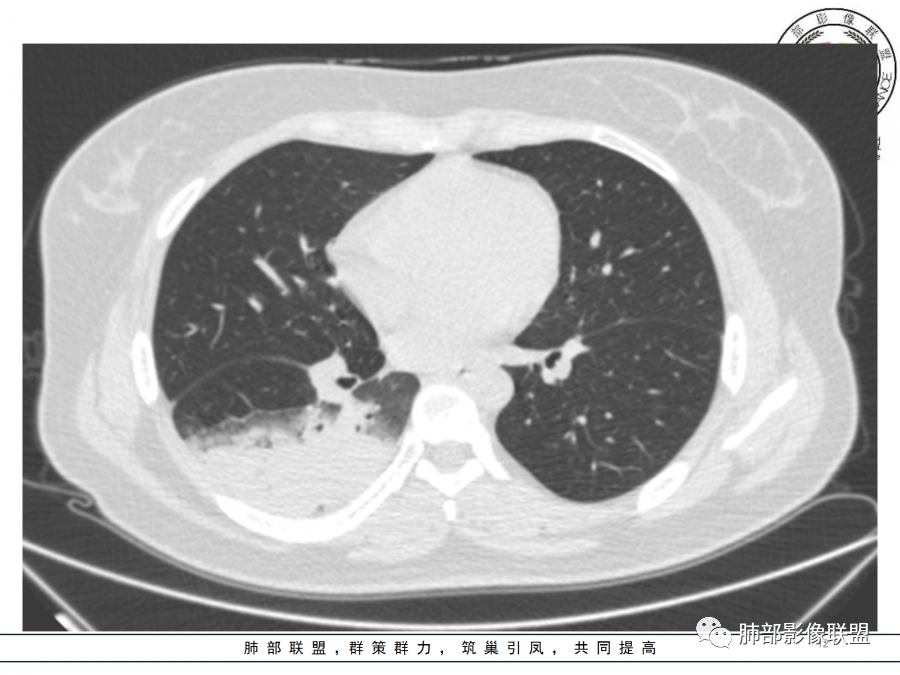

右肺胸膜下实变,病变跨多个叶生长,宽基底与胸膜相连,近端支气管穿行病灶内,并可见片状磨玻璃影,边界清,部分远端小支气管堵塞,支气管略有扩张,周围散发小结节,临床年轻女性,炎性指标高,发热六日,首先考虑感染性病变(肺链,奴卡,隐球,OP)鉴别淋巴瘤。

年轻女性,无明显诱因发热,体温略高,起病较急,有畏寒,右下肺紧贴胸膜下片状实变影,部分融合,外围有结节影,性质比较单一,类似于蘑菇兄弟,病灶周围伴有晕,支气管进入近端扩张远端堵塞,常规考虑感染,肺炎链球菌、隐球菌。

青年女性,发热咳嗽5天,炎症标志物升高。右肺下叶大片实变伴周围GGO,GGO内未见细网格,主体与胸膜平行,似多个病灶融合,实变区内见支气管部分进入,部分支气管受压狭窄,周围可见多发卫星病灶。支持炎性,考虑隐球感染,鉴别op。

年轻女性,急性发病,咳嗽咳痰五天,炎性指标升高,右肺下叶胸膜下大片实变影,周围见磨玻璃影,边界清晰,长轴与胸膜平行,呈融合趋势,支气管进入走行自然,远端截断,考虑炎性,隐球菌可能。

26岁,女性,发热、咳嗽5天。咳少量黄痰,起病急,病程短,白细胞及中性高,血沉及D-二聚体增高。胸部CT:右肺下叶大片实变,长轴沿胸膜分布,宽基底与胸膜接触,边界不清,周围GGO,部分团片影融合,病灶内可见支气管充气征,部分支气管进入病灶后阻塞。考虑:感染性病变,隐球菌?脓毒肺栓塞?鉴别:肺炎型肺Ca。

细菌性肺炎是沿着支气管往周围肺泡散开,内朝外,沿着叶段分布,受到支气管管辖,呈扇形,与支气管长轴平行,与胸膜垂直,隐球菌就是外朝内,外就是肺小叶内的肺泡,外周的。

肺小叶。他就是一个个肺小叶的融合,胸膜平行,和病毒一样。只是病毒在间质,是肺小叶分布的毛玻璃。隐球菌是肺实质,肺泡,肺小叶的实变。

这个病变也不是一个起源中心,胸膜下,多发结节状、实变影。而大叶性肺炎多数由内-外大片状。所以是肺实质多发融合病变。单纯从影像上,还是比较符合隐球菌特点,胸膜下,多发、多中心,相互融合(兄弟齐心)。

隐球菌,胸膜下病灶,多个起源中心,最终还是融合在一起,侧向融合为主的。

隐球菌,侧向融合、外围胸膜下为主,也有累及叶段的、比较少。

隐球菌之顺口溜(影像征像版)在那遥远的边远山区——胸膜下生活着一群蘑菇兄弟——性质相同多结节表面虽脏,内心实诚——有晕,一般无空洞扮扮鬼脸,偶尔调皮——鬼脸征撞墙就跑,颇有灵性——一般不引起胸膜增厚积液气管通畅或进门才堵,只为空气——不会堵门口周围蔓延,不乱播散,死心踏地——不走淋巴,气管,血道播散。污头垢面,家里干净,只因免疫不低,神采奕奕——空洞干净,注意:以上不适用于免疫力低下病人。